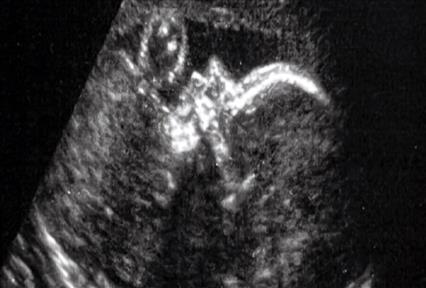

Από τα πρώτα στάδια της ανάπτυξης, όπως φαίνεται στο βίντεο, τα καρδιακά κύτταρα ενός έμβρυο ποντικού αρχίζουν να οργανώνονται αυθόρμητα σε σχήμα που μοιάζει με αυτό καρδιάς